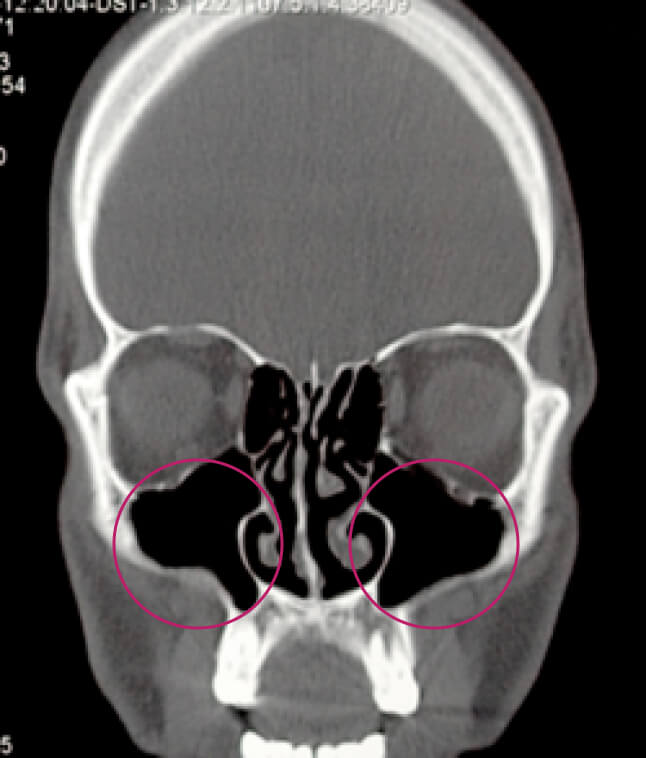

Сүүлийн жилүүдэд мэргэжилтнүүд харшлын ринит ба олон төрлийн хамар, хамрын дайвар хөндийн үрэвсэл хоорондын харилцаа хамаарлын талаар их ярьдаг болж. Энэхүү харилцаа холбооны механизм гүйцэд сайн судлагдаагүй байгаа ч харшлын риниттэй өвчтөнүүдэд архаг хамар, хамрын дайвар хөндийн үрэвсэл үүсэх магадлал өндөр гэж үздэг.

Компьютер томографын доорх зурагт хамрын дайвар хөндийн (хөндлөн зүсэлт)-ийг харж болно. Эрүүл хүнд (зүүн талынх) дээд эрүүний хонх нь цэвэр, өргөсөөгүй, салс зузаараагүй, хонх хэсэгт саарал сүүдэр ажиглагдаагүй байна. хамар, хамрын дайвар хөндийн үрэвслийн үед (баруун талын зураг) КТ-т эрүүний хонхнуудын доод хэсгүүдэд ихэнхдээ тэгш бус ирмэгтэй нягт сүүдэр тодорхойлогдож байна. Хамрын суваг салс хавагнасан байна.